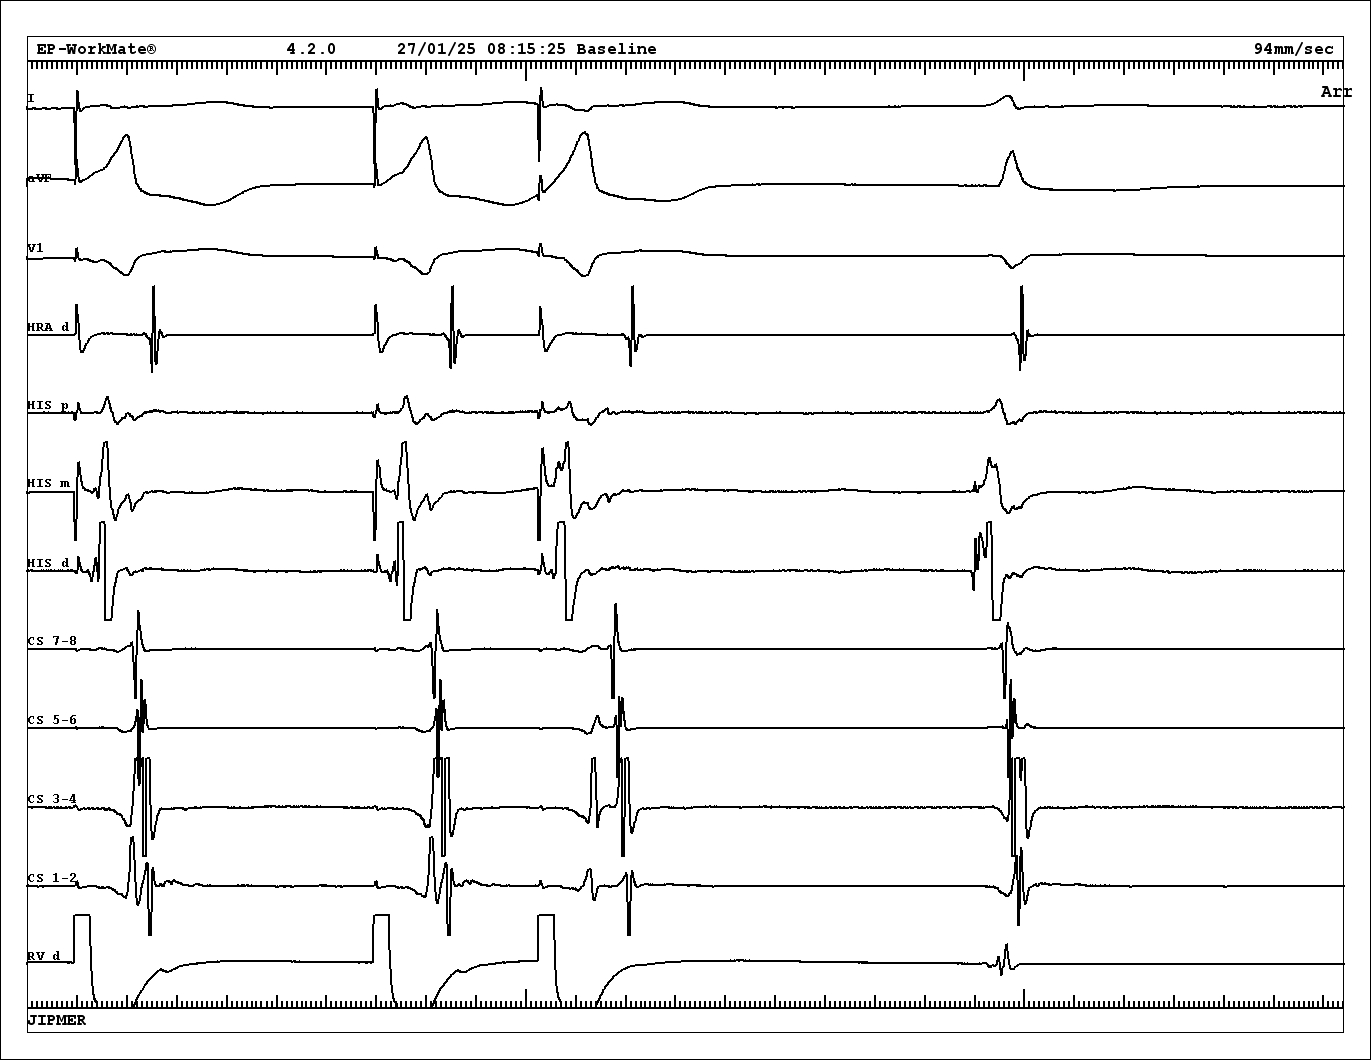

Case 2 - 42 F - Tachy induced with A extra. VA 126

tachy.jpg

PVC on time with His

pvc.jpg

VOP from base - cPPI-TCL 140 ms

vop_base.jpg

VOP from apex - cPPI-TCL 180 ms

vop.jpg

VA from base and apex

va_base_apex.jpg

Diagnosis

• Atypical AVNRT

• Bystander concealed nodoventricular AP

• Successful ablation at RIE